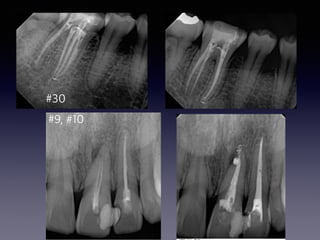

#6,#7,#8,#9,#29

partial pulputomy

follow-up case

(48 female)

2013 05 20

31

2013 06 28

15m later

2013 06 12